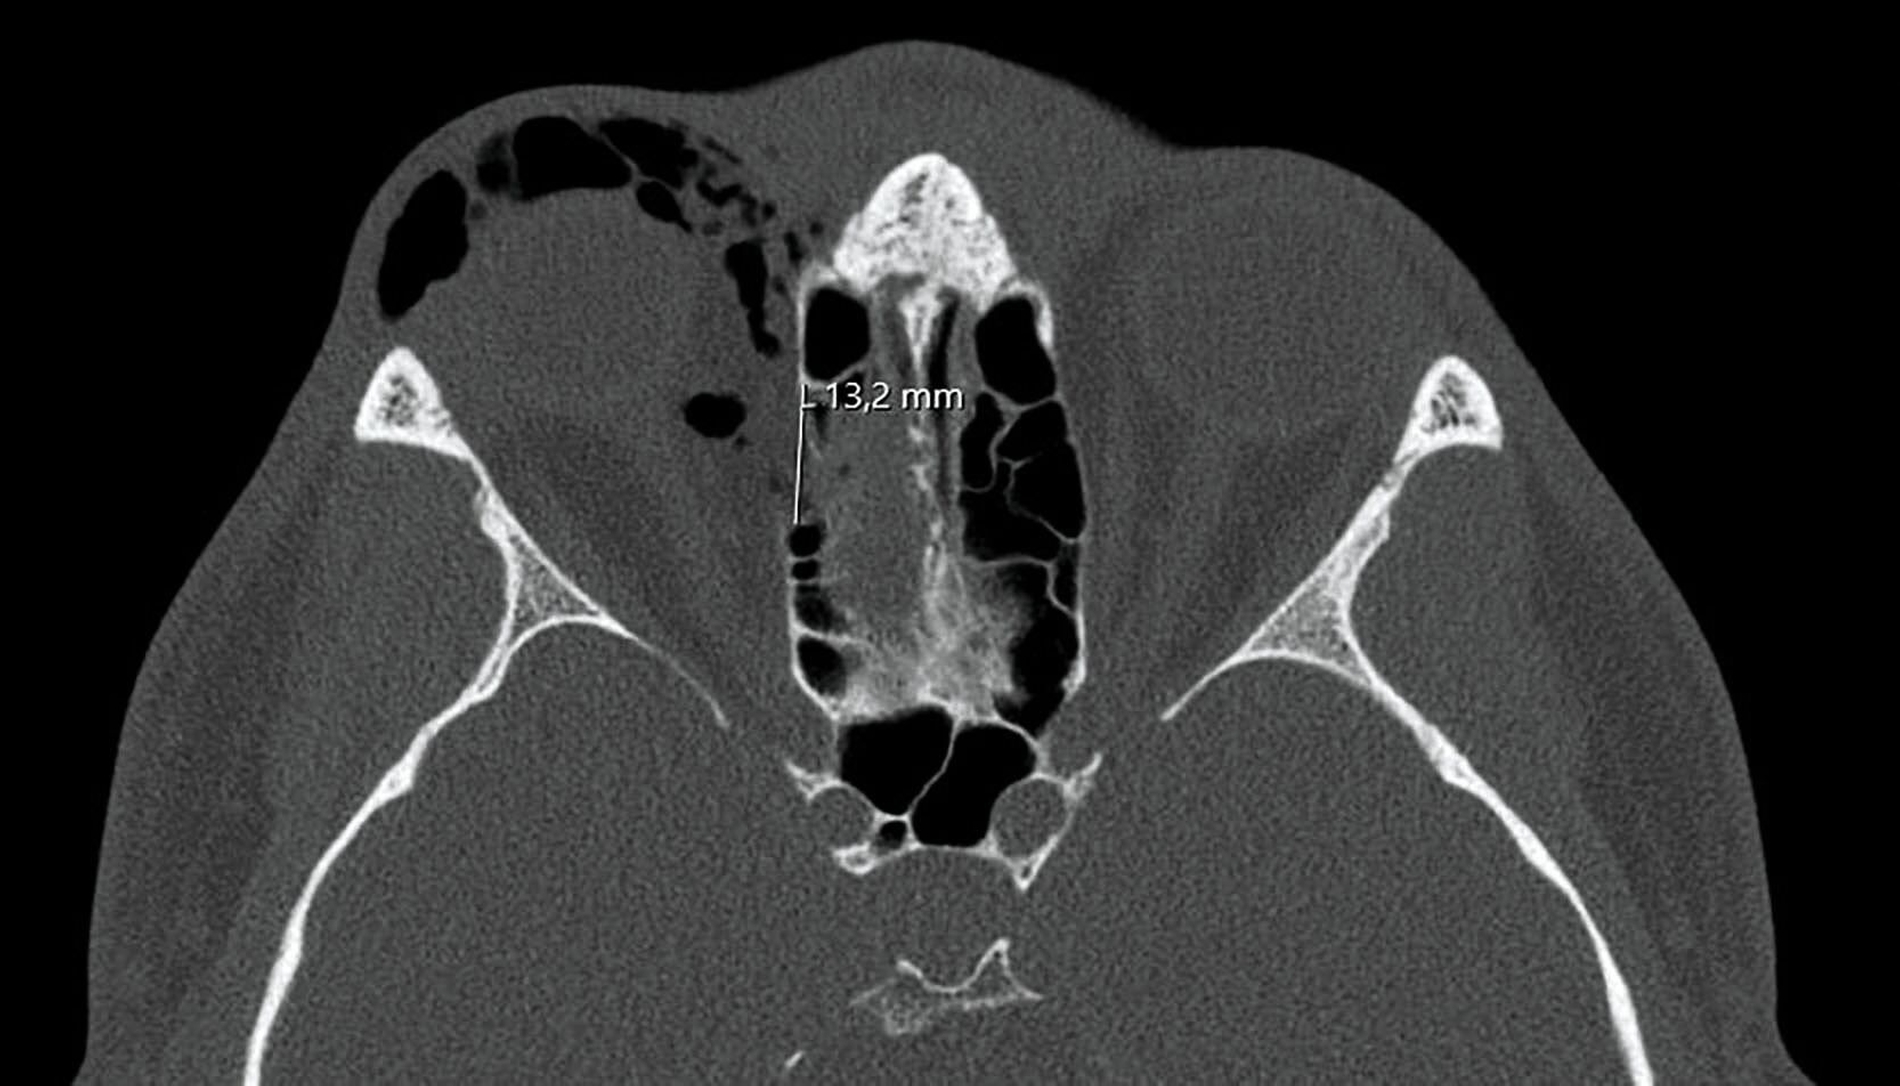

Nach der eingehenden klinischen Untersuchung wurde zur weiteren Diagnostik eine Computertomografie (CT) durchgeführt, die die Verdachtsdiagnose einer Fraktur der rechten Orbita bestätigte. Die CT-Bilder zeigten eine Fraktur der dünnen seitlichen Wand des Siebbeinlabyrinths (Lamina papyracea) mit Herniation des orbitalen Fettgewebes sowie eine geringfügige Vorwölbung des Musculus rectus lateralis in den Knochendefekt. Zudem war ein ausgeprägtes Weichgewebsemphysem sichtbar (Abbildung 1). Weitere Frakturen konnten ausgeschlossen werden.